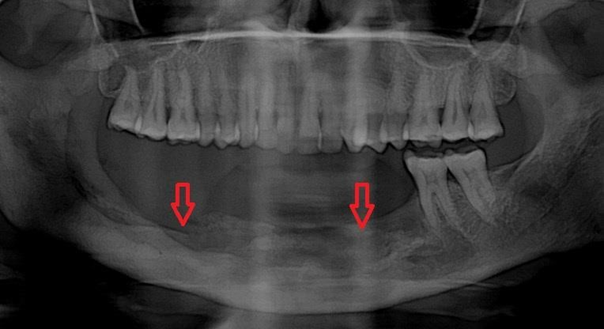

Case 1: He was a 39 year old male presented with left jaw pain for two months. He was diagnosed with Covid-19 pneumonia and required oxygen with dexamethasone at a dose of 6mg twice a day followed by once a day for total 14 days eight months ago. Due to his jaw pain he consulted dentist before coming to our instituition and underwent left 3rd molar extraction. Following the procedure his symptoms did not improve rather worsened. Pain and swelling increased gradually and there was oozing from the tooth extraction site. He did not have any sinus symptoms and underwent CT scan which revealed left mandibular osteomyelitis (Figure 1). No sinus tenderness was present and sinus endoscopy showed normal mucosa. HbA1C was 9.2%. Debridement of left mandible with extraction of corresponding molars was done. Histopathology from the debrided tissue showed aseptate, broad fungal hyphae with obtuse angle branching with bony and angioinvasion characteristic of mucorales (Figure 2). However fungal culture was negative. He was treated with 2 weeks injection amphotericin - b lipid emulsion which he tolerated well without any toxicity.

Figure 1 A- CT mandible - left mandibular osteomyelitis with expansion of the cortex, B- CT paranasal sinuses – normal.

Symptoms resolved and wound became healthy. He was started on tablet posaconazole. Trough level was done after 7 days and it was 1606 ng/ml. Total 3 months of oral therapy was completed and he did well on follow up.